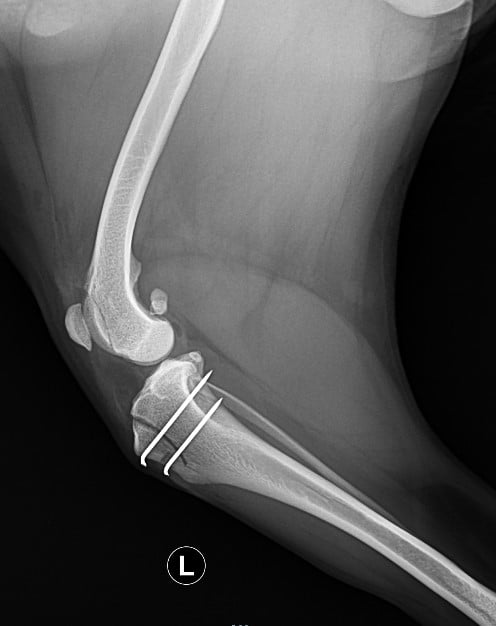

Diagnosen stilles klinisk ved en grundig undersøgelse af knæet, hos os vil vi også tage røntgen for at vurdere fejludviklingen i lårben og skinneben, sjældent vil vi være nødt til at lave CT scanning.

Operationsmetode afhænger af forandringerne, men som oftest vil man flytte senen fra patella og gøre gruben som patella løber i dybere.